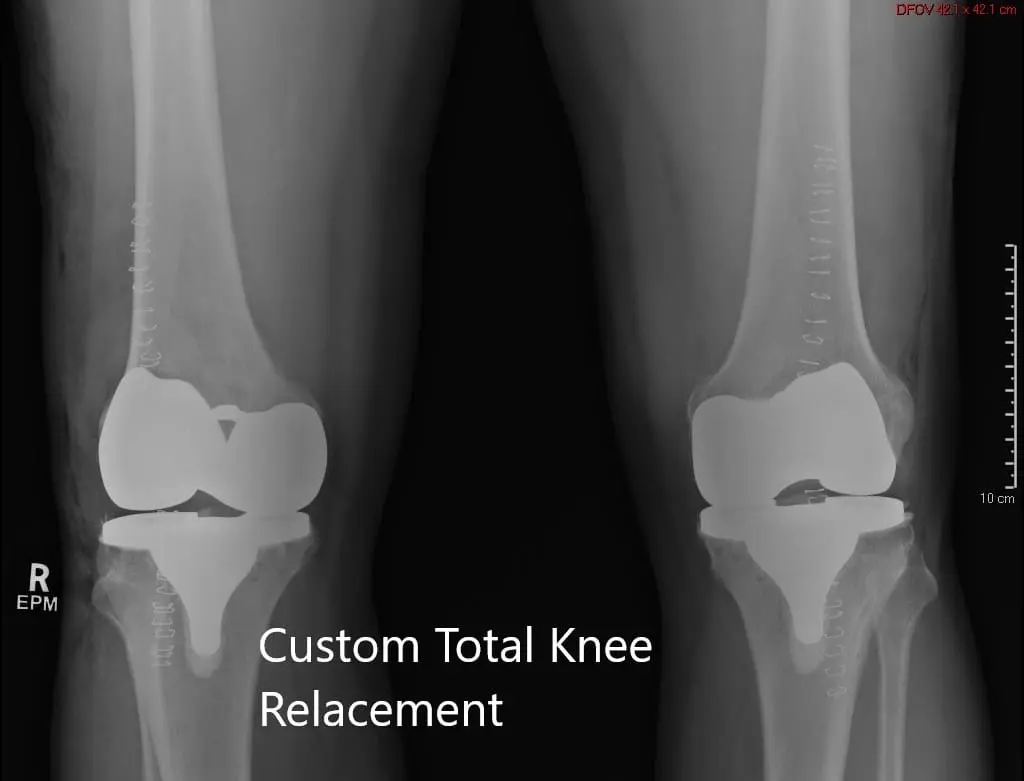

Postoperative X-ray showing the AP view of both knees

Postoperative X-ray showing the AP view of both knees.